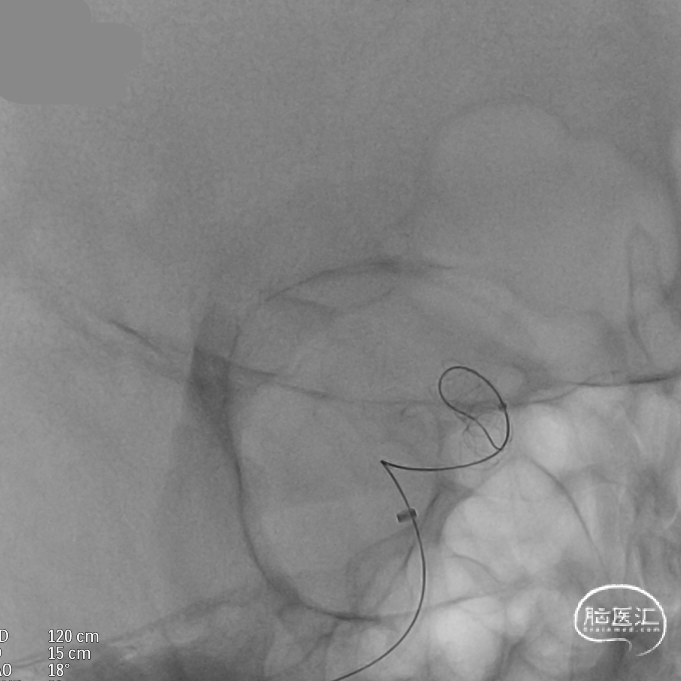

支架到位,原位释放,前段打开。

造影确认支架远端打开充分,贴壁良好,继续推送支架。

支架全部释放,调整张力,微导管通过支架,回收输送导丝。

支架内使用成襻微导丝进行按摩,使支架充分贴壁。